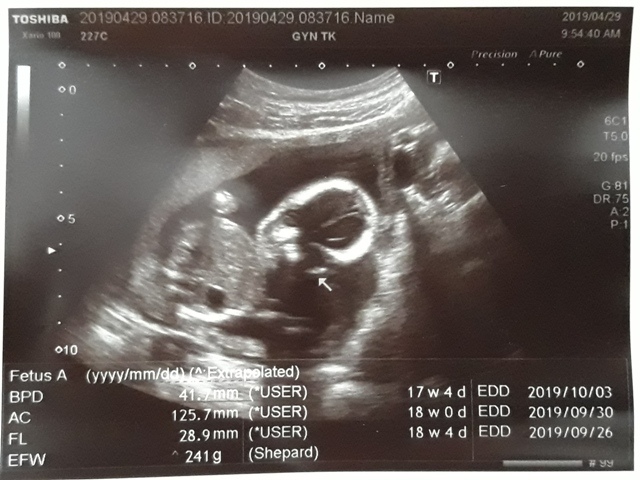

| 仙人掌(2019/04/29)的真心話 星期一 天氣晴 編號19-110 |

『脊髓性肌肉萎縮症』(SMA,俗稱漸凍人)、『X染色體脆折症』(FXS)這兩項,檢查的結果,一切正常。

SMA、FXS的檢查結果,都正常↓

近三次產檢資料統計

| 日期/項目 | BPD | AC | FL | EFW | 心跳 |

| 2019年03月04日 | 無資料 | 無資料 | 無資料 | 無資料 | 無資料 |

| 2019年04月01日 | 28.9mm | 77.9mm | 14.2mm | 107g | 153 |

| 2019年04月29日 | 41.7mm(44%) | 125.7mm(61%) | 28.9mm(103%) | 241g(125%) | 150 |

| BPD:胎兒頭骨橫徑 AC:胎兒腹圍的長度 FL:胎兒大腿骨的長度 EFW:胎兒的體重 | |||||